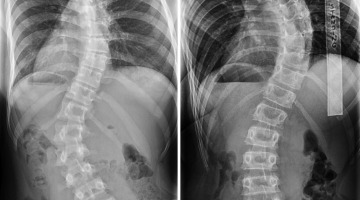

Σκολίωση - Schroth